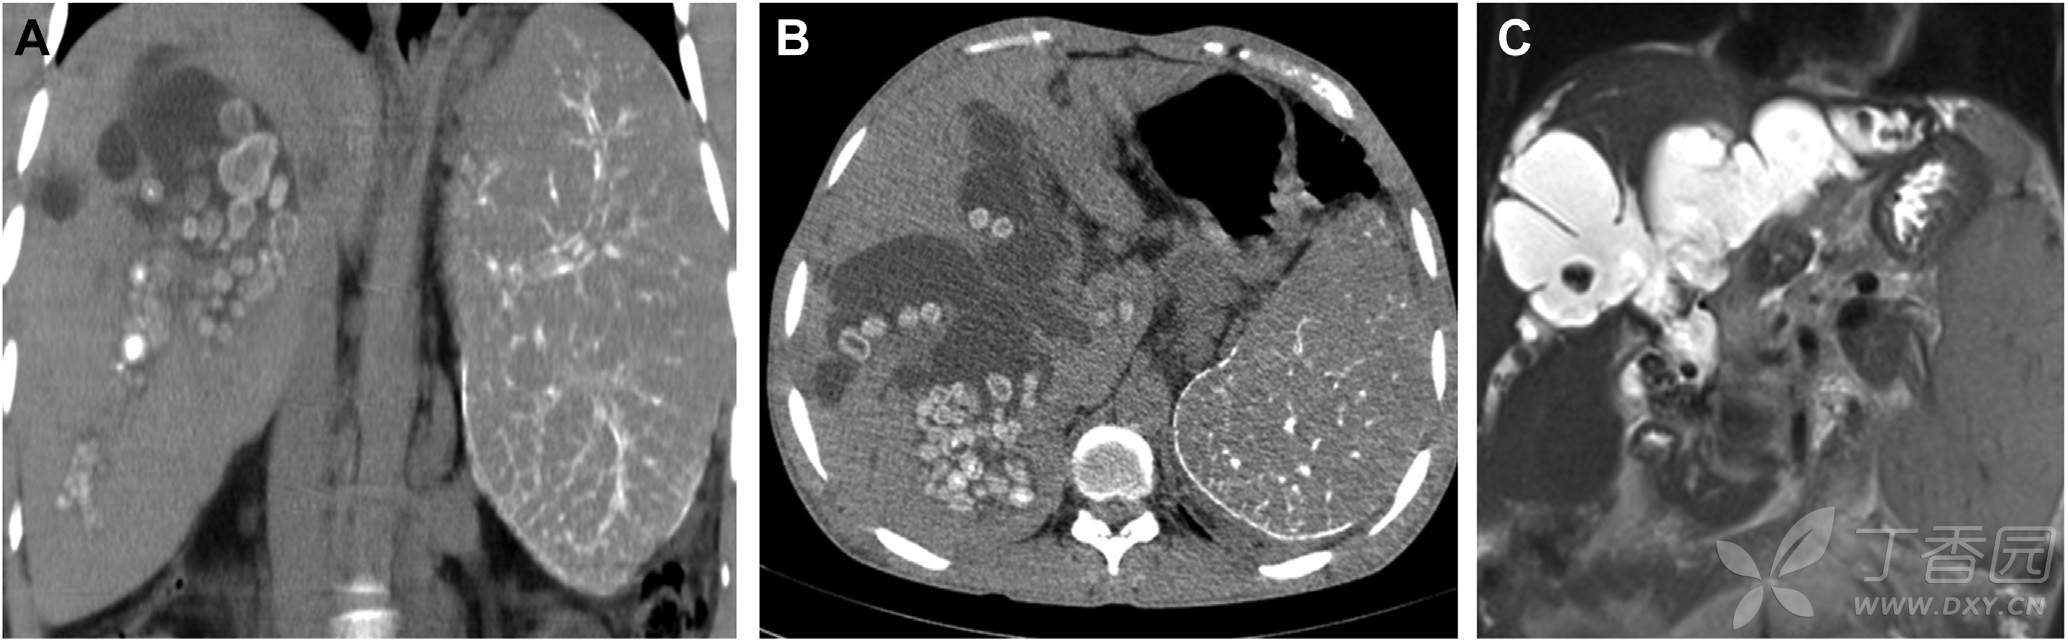

腹部CT平扫所见如图A、图B,MR检查如图C。胃镜检查提示Ⅱ级食管静脉曲张。

请问:诊断是什么?

A 肝内胆管结石 B 肝门部胆管癌 C Caroli病 D 门脉周围纤维化致门脉高压症